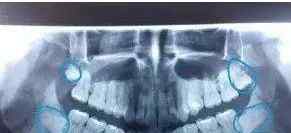

智齿在x光片上非常清晰↓ⅵ